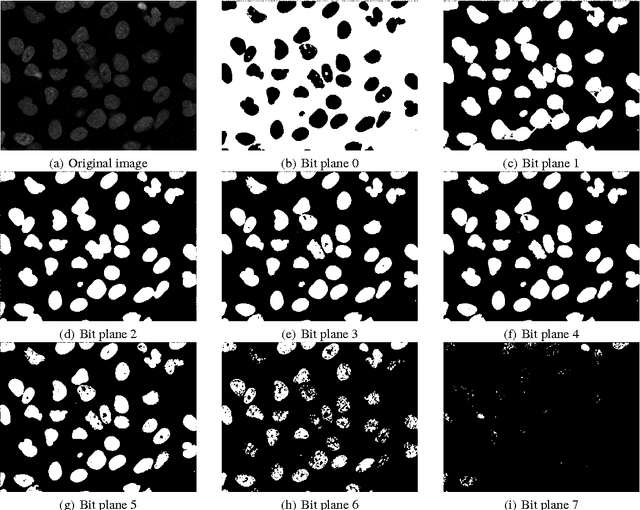

Abstract:In this paper, we propose an approach to the unsupervised segmentation of images using Markov Random Field. The proposed approach is based on the idea of Bit Plane Slicing. We use the planes as initial labellings for an ensemble of segmentations. With pixelwise voting, a robust segmentation approach can be achieved, which we demonstrate on microscope cell images. We tested our approach on a publicly available database, where it proven to be competitive with other methods and manual segmentation.